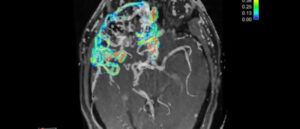

Субдуральная гигрома

Травмы головы, даже средние по тяжести, могут провоцировать образование, называющееся гигрома головного мозга. Это доброкачественная опухоль, состоящая из серозной жидкости, слизи и белка. И если гигрома на ноге или руке не несет в себе опасности для жизни, то новообразования в головном мозге чреваты серьезными осложнениями. Поэтому при ухудшении самочувствия следует немедленно обращаться за медицинской помощью …